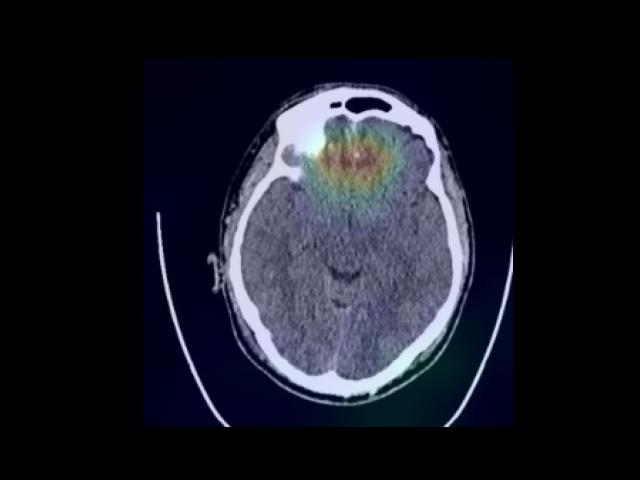

Sample Gallery